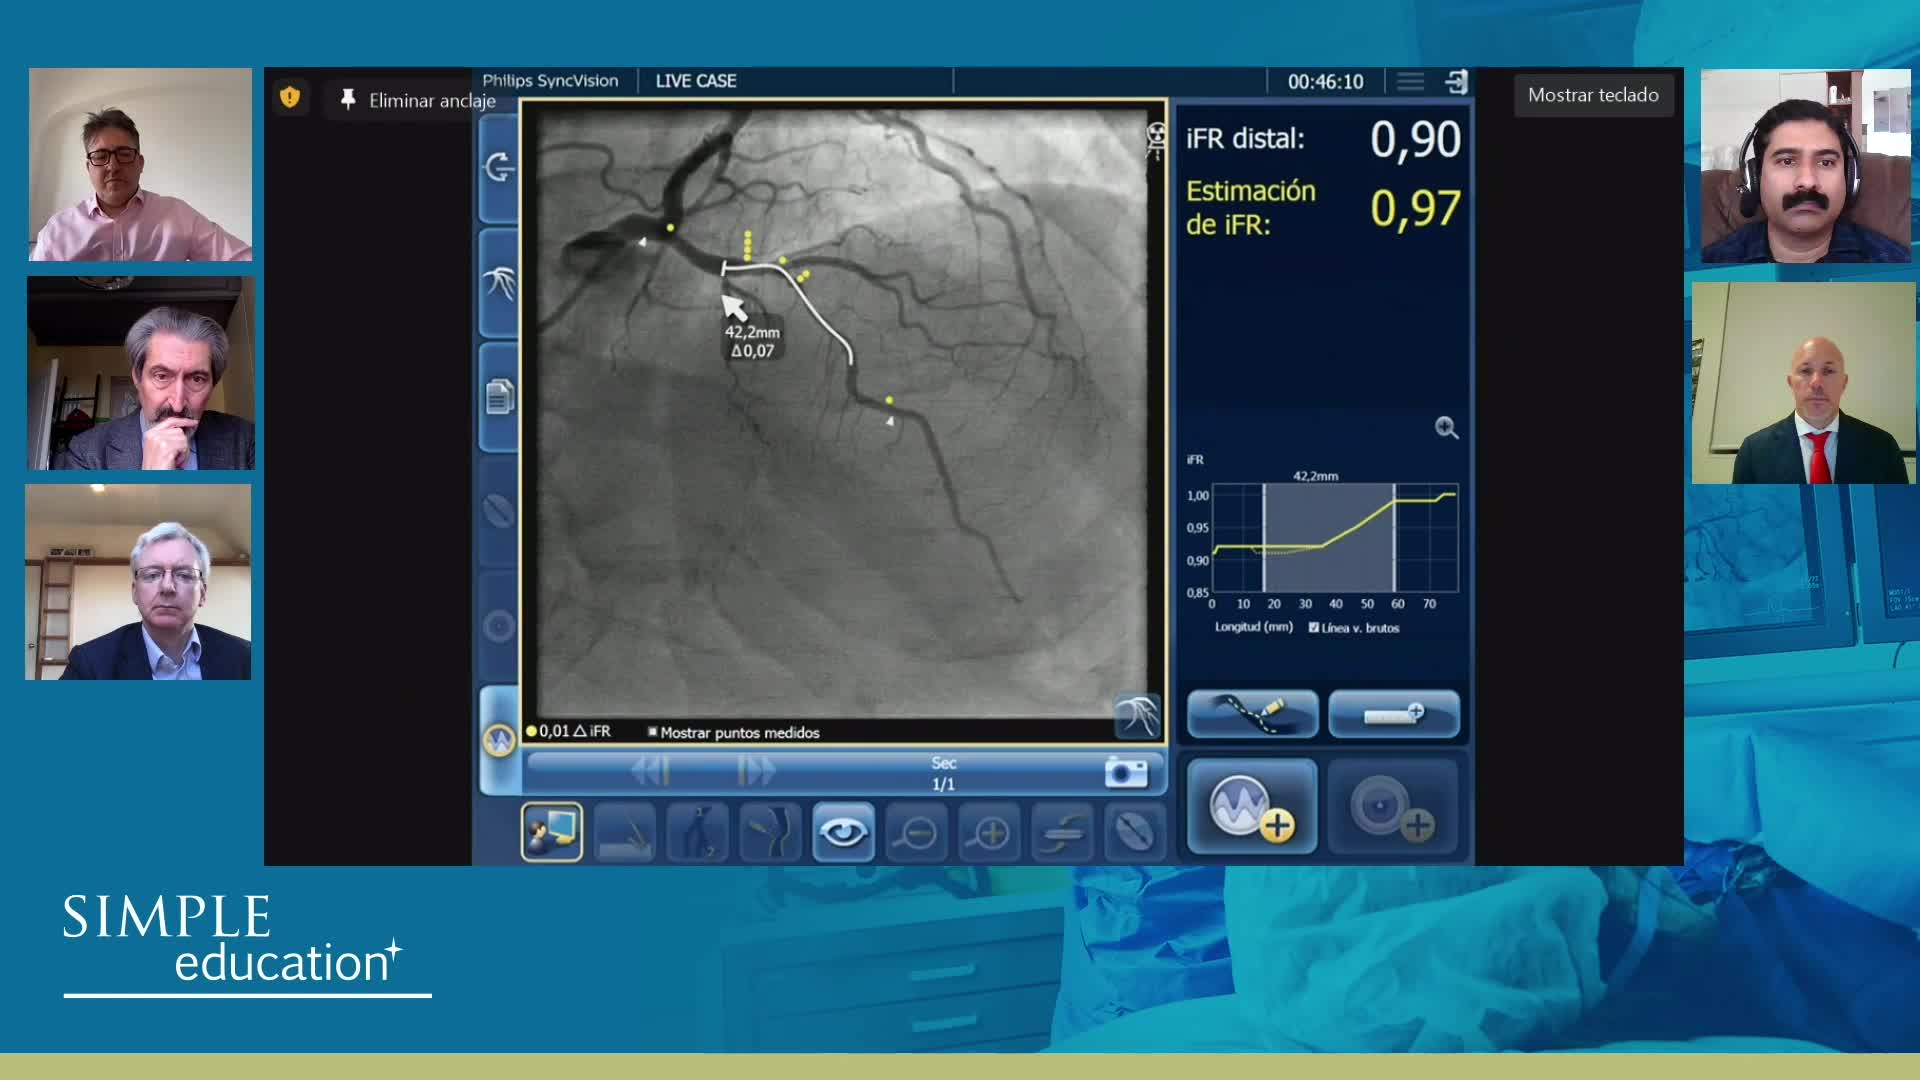

Advances in Co-registration, Coronary Physiology & Intra Coronary Imaging - April 2024 Day One

Advances in Co-registration, Coronary Physiology & Intra Coronary Imaging - April 2024 Day Two

Advances in Co-registration, Coronary Physiology & Intra Coronary Imaging - November 2023 Day One

Advances in Co-registration, Coronary Physiology & Intra Coronary Imaging - November 2023 Day Two

Understanding how SyncVision differs from other co-registration based technologies - Dr Justin Davies

How to perform good co-registration measurements using iFR and IVUS - Prof Carlo Di Mario

Using SyncVision Co-registration to distinguish between focal and diffuse coronary disease. - Prof Giuseppe Tarantini